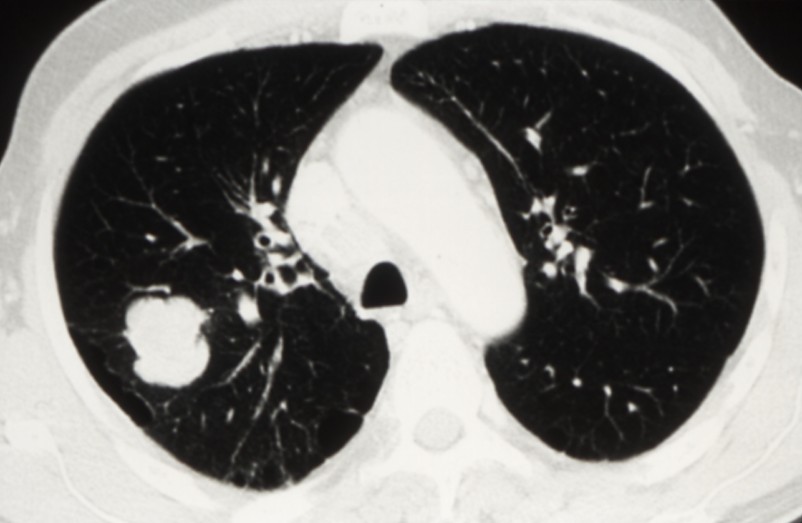

Cancers bronchiques